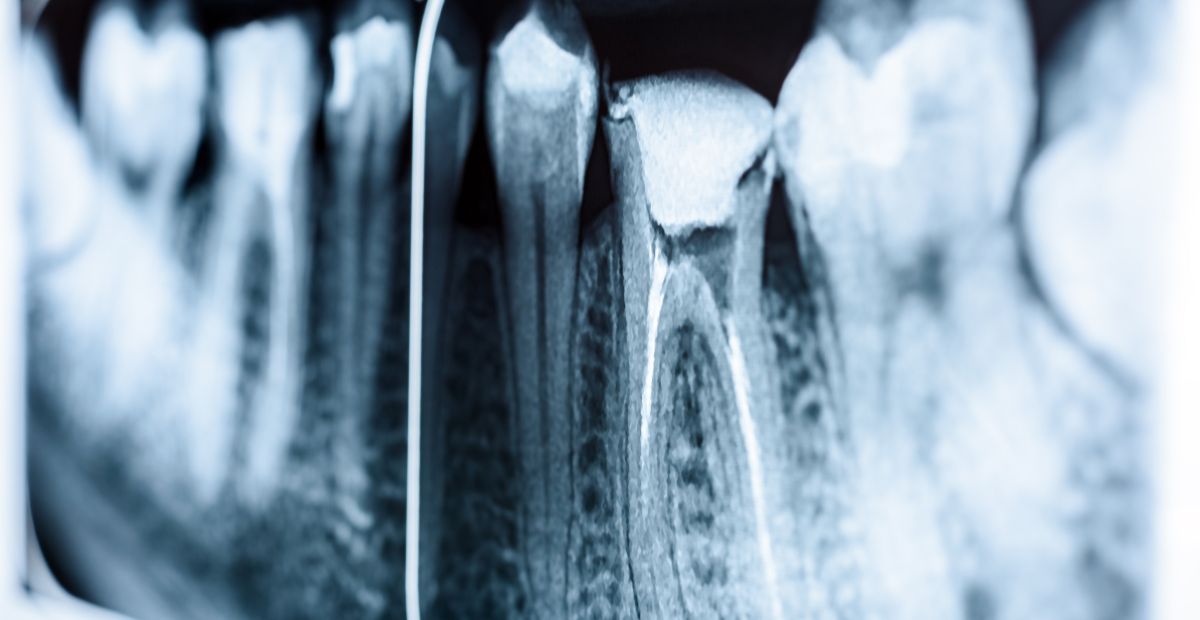

La endodoncia (o tratamiento de conductos) es un procedimiento dental que trata el interior del diente cuando la pulpa nerviosa está infectada o inflamada. Nuestro objetivo es eliminar el foco de infección, conservar el diente y aliviar el dolor, sin necesidad de extracción.